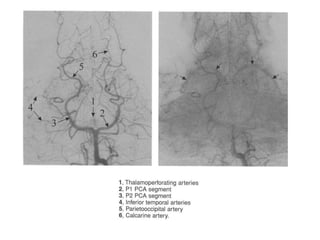

Ramos perfurantes

• Diretos e circunflexos

• Os ramos perfurantes diretos incluem as artérias

talomoperfurantes as artérias talamogeniculadas e perfurantes

pedunculares .

• As tamoperfurantes originam-se de P1(geralmente no terço

médio) e entram no encéfalo pela SPA; nascem no aspecto

posterior de P1 e na maioria dos casos, representa a maior ramo

desse vaso.

• As talamoperfurantes irrigam porção posterior do tálamo,

hipotálamo, subtálamo e parte do mesencéfalo (incluindo

substância reticular)

• O quadro clínico produzido por lesão das

talamogeniculadas incluem: distúrbios somestésicos,

fraqueza motora, déficit de memória, disautonomia,

diplopia, paresia do III par + tremor rural (síndrome de

Nothnagel).

• As perfurantes pendunculares nascem de P2 e

direcionam-se ao pedúnculo cerebral, irrigam os tractos

corticoespinhais e corticobulbaregs

• Os ramos circunflexos originam de P1 e P2, os curtos

irrigam os corpos geniculados, os longos (artérias

coliculares), os folículos.

• As talamogeniculadas originam-se diretamente de P2,

diretamente abaixo do tálamo lateral e penetram na

cisterna circundante. Irrigam a metade posterior do

tálamo lateral e a perna posterior da cápsula interna e o

trato óptico. O infarto produzido por essas perfurantes

desencadeia a Síndrome de Dejerine e Roussy: perda

contralateral das sensibilidade superficial e profunda,

dor intensa, hemianopsia homônima.